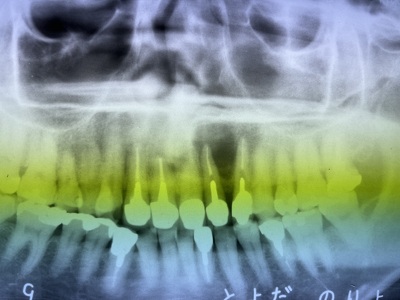

患者さんは静岡県からお出でになりました。レントゲン写真の右上2番の治療を依頼されました。

レントゲンでは上手く治療できているように見えますが治療結果は悪く、たびたび化膿を繰り返し、抜歯を進められていました。

当院で治療後のレントゲンです。根の尖にあった病巣が消失しています。